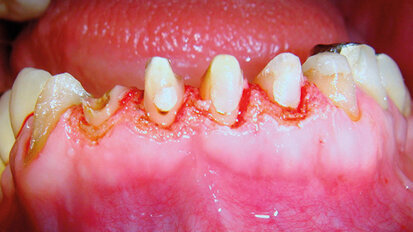

Gengivoplastica con laser a diodo: rapidità, efficacia, mininvasività e predicibilità

Il rimodellamento delle parabole gengivali è una terapia chirurgica molto spesso necessaria per ottimizzare al meglio le linea del sorriso dei pazienti, al...